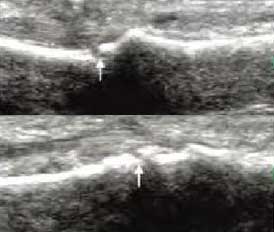

3、准确判断关节积液增加,精准判定RA严重程度

类风湿关节滑膜炎症会导致滑液渗出不断增多,形成关节腔积液。肌骨超声最少可发现1ml的积液,能对关节腔积液量及位置准确定位,通过检测判定关节腔内液性边界清楚的无回声区、细点状回声或细微的低回声条纹,判断其宽度和深度衡量积液量的多少,进而评估RA的严重程度。

Ⅰ级微量积液

滑膜囊内见前后径3.55mm液性暗区,呈椭圆形

Ⅱ级较多量积液

暗区内有团状高回声,可见深度达6.46mm液性暗区

Ⅲ级大量积液

关节囊扩张,可见大范围液性暗区,髌上囊积液深度达11.2mm